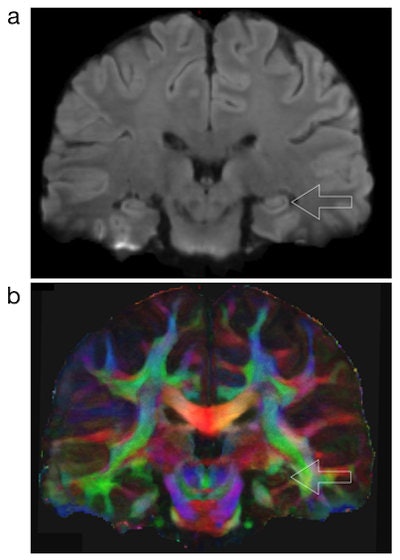

The process is a multishot diffusion-weighted imaging (DWI) technique known as multiplexed sensitivity-encoding (MUSE). So far, MUSE has demonstrated the potential to reduce motion artifacts and produce multiple types of MRI data, such as information on iron levels, gray-matter volume, and white-matter connectivity, according to the university.

Chen and colleagues previously studied the protocol's performance using 3-tesla MRI scanners and healthy adult volunteers. At that time, they reported that MUSE "should prove highly valuable for mapping brain structures and connectivities at high spatial resolution for neuroscience studies" (NeuroImage, May 15, 2013, Vol. 72, pp. 41-47).

To evaluate patients with Parkinson's disease, an MRI scan acquires long-exposure images, which can add noise and reduce image quality. To combat this, MUSE's noise-limiting process has been shown to reduce noise-related errors by as much as 90%. In addition, by alternating scan direction (top down versus bottom up), MUSE can address distortion and improve quality, according to UA.